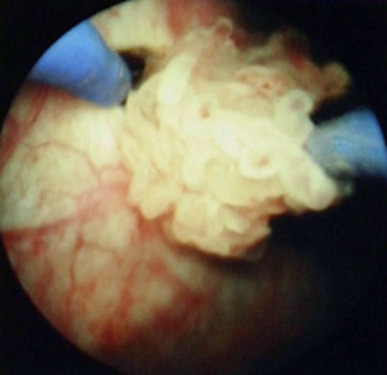

腔内泌尿外科彩色图谱(精)

作者 谷现恩//刘瑞强//闫治安